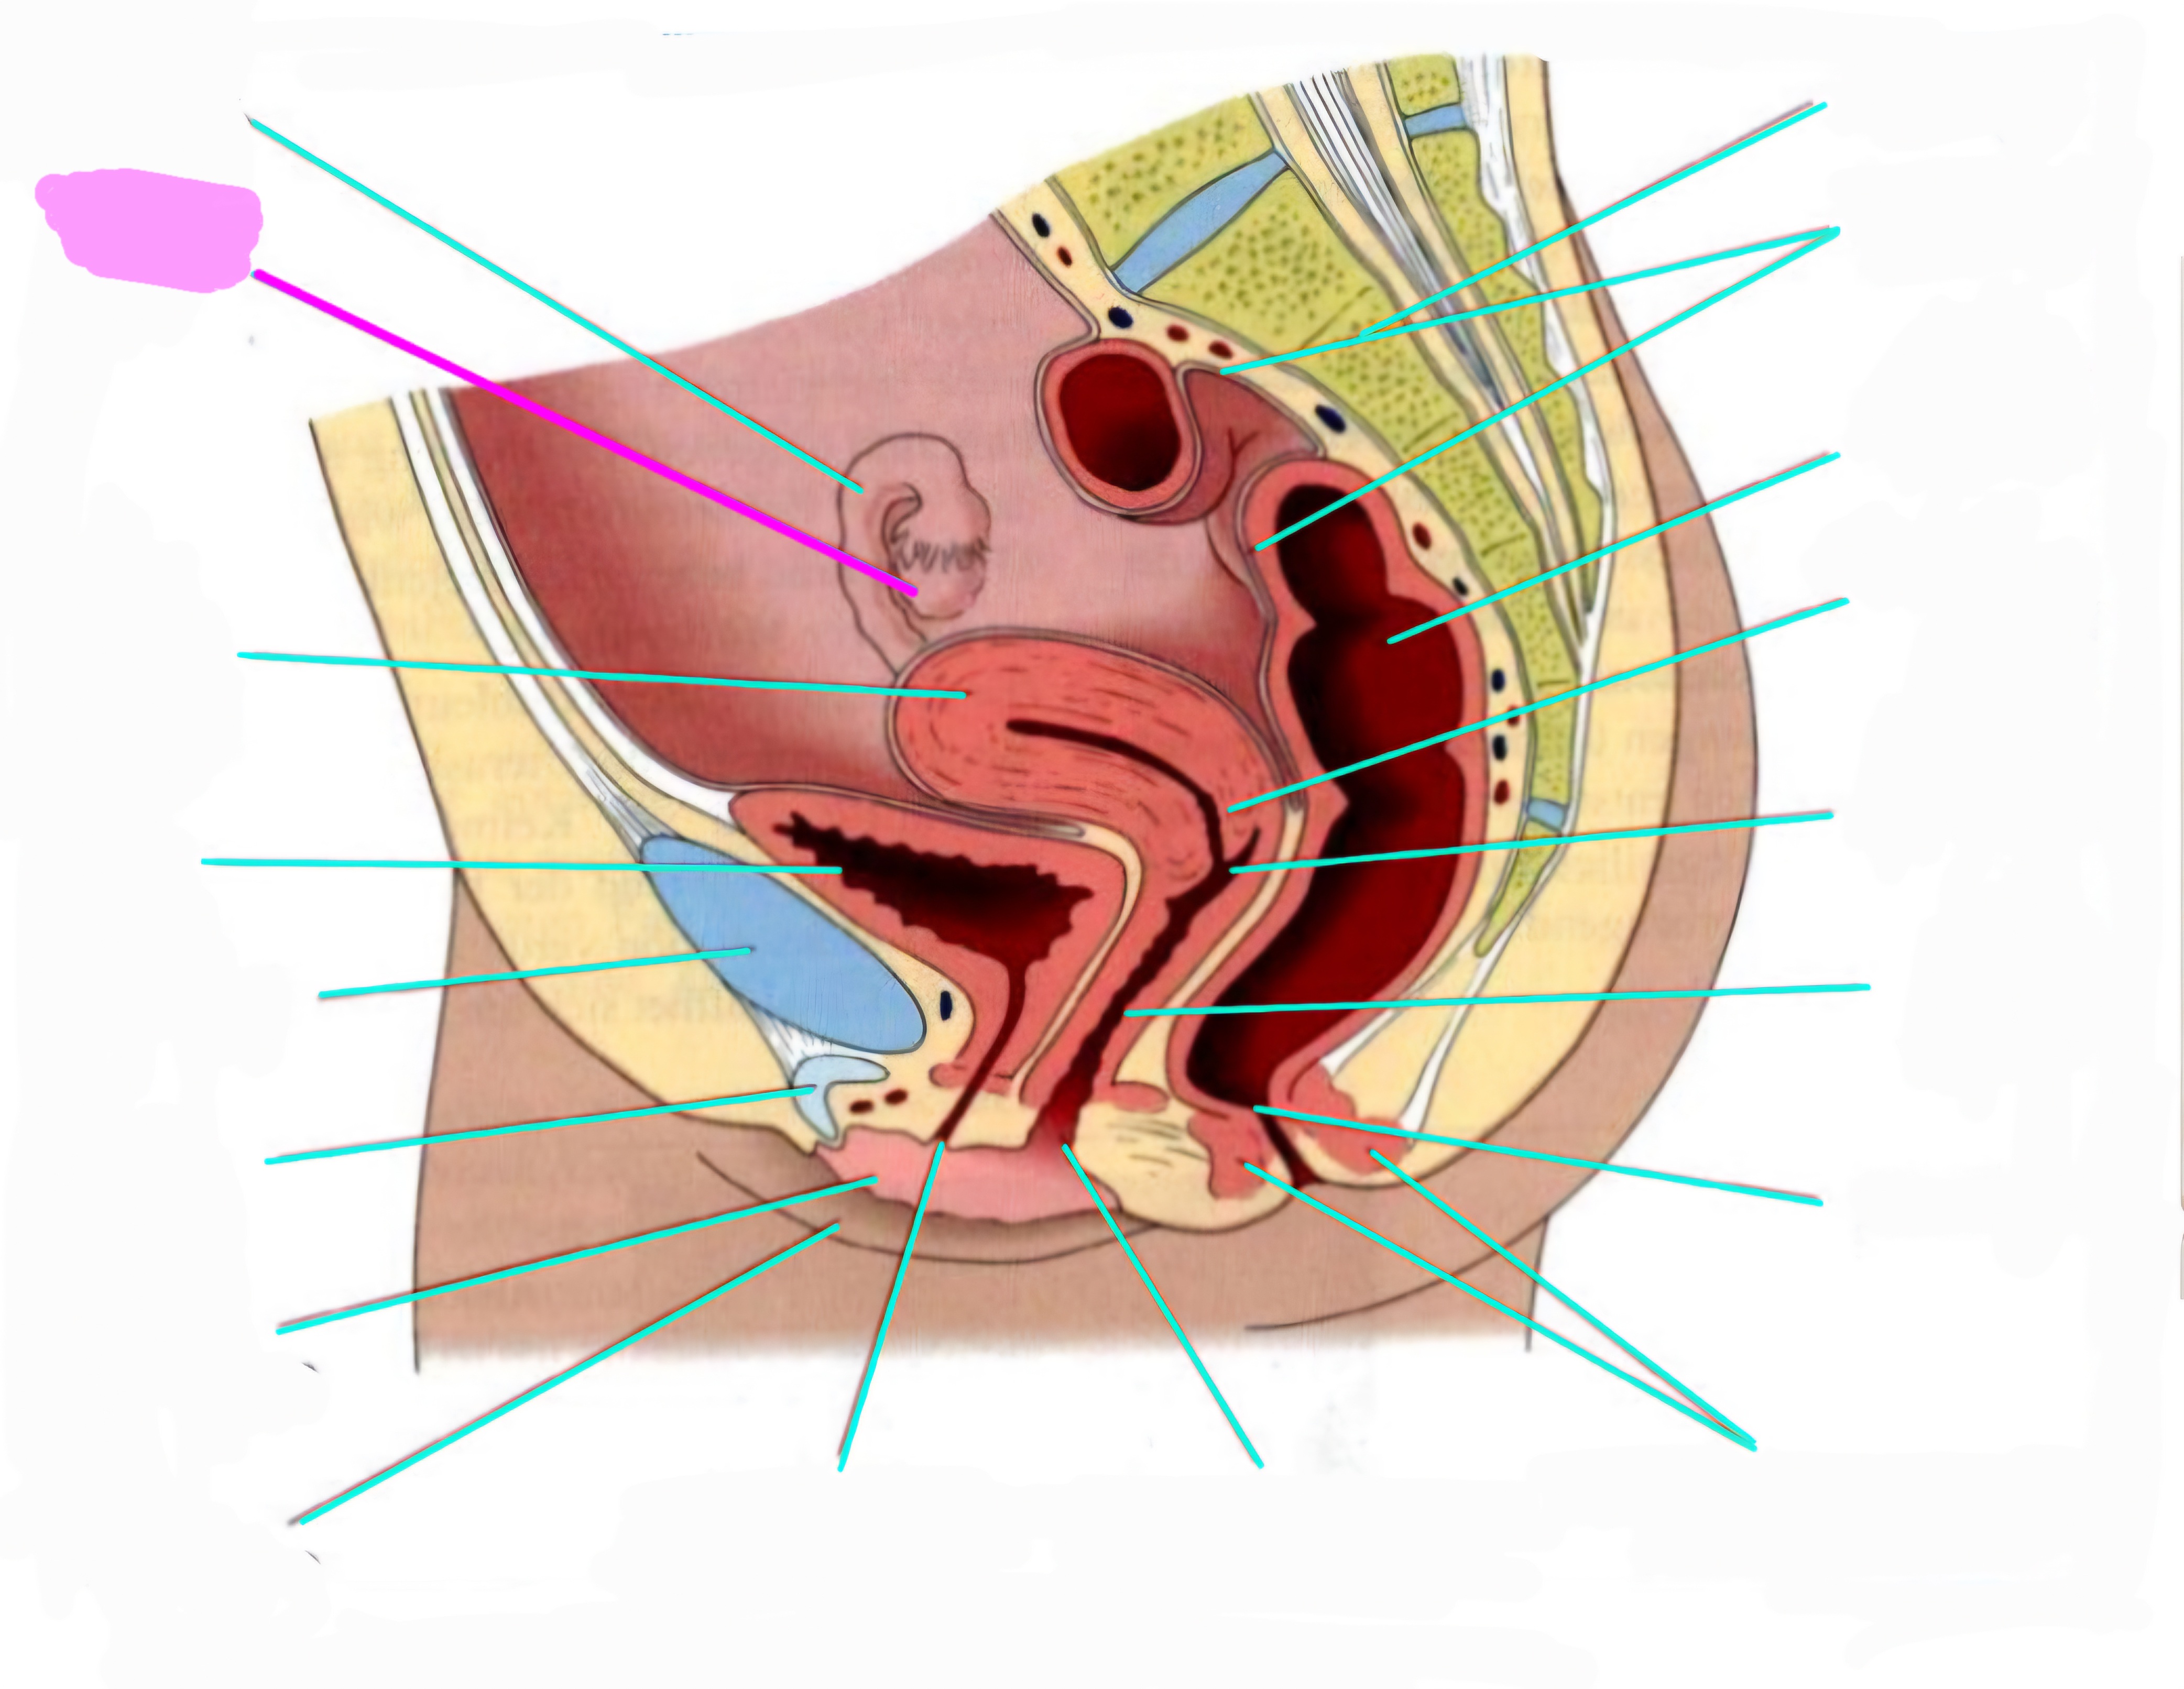

wbl. genital Anatomie

19 Terms

Tubea uterina (Eileiter)

Ovar (Eierstock)

Uterus (Gebärmutter)

Vesica Urinaria (Harnblase)

Symphyse

Klitoris

Labia minor pudendi (kleine schamlippen)

Labia Majoran pudendi (große Schamlippe)

Urethra (Harnröhre)

Introitus vaginae (Scheideneingang)

Sphincter ani externes (äußere Afterschließmuskel)

Anus (After)

Vagina (Scheide)

Portio (äußerer Muttermund)

Rektum (Mastdarm)

Zervix (Gebärmutterhals)

Peritoneum (Bauchfell)

Os sacrum (Kreuzbein)